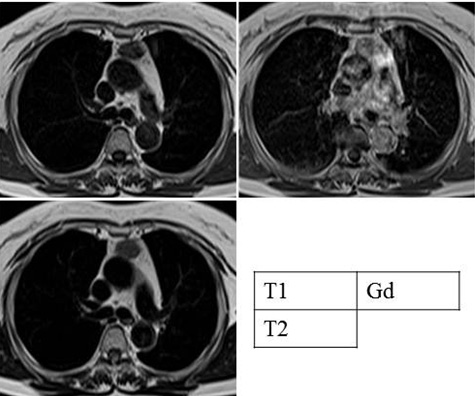

A 69-year-old woman visited our hospital complaining of neck discomfort. Computed tomography (CT) showed no abnormal shadows in the neck, but a 2.5 cm tumor was detected in the anterior mediastinum (Figure 1). Chest radiography did not reveal an abnormal shadow (Figure 2). Magnetic resonance imaging showed a low-signal intensity on T1-weighted images, iso-signal intensity on T2-weighted images, and a heterogenous pattern on gadolinium-enhanced images (Figure 3). Abnormal hyper uptake (maximum standardized uptake value [SUVmax] = 9.72) was found at the tumor on positron–emission tomography (Figure 4). The tumor was suspected to be an invasive thymoma or thymic carcinoma.

Figure 3: Magnetic resonance imaging (MRI) showed low-signal intensity on T1-weighted images, iso-signal intensity on T2- weighted images, and a heterogenous pattern on gadoliniumenhanced images.